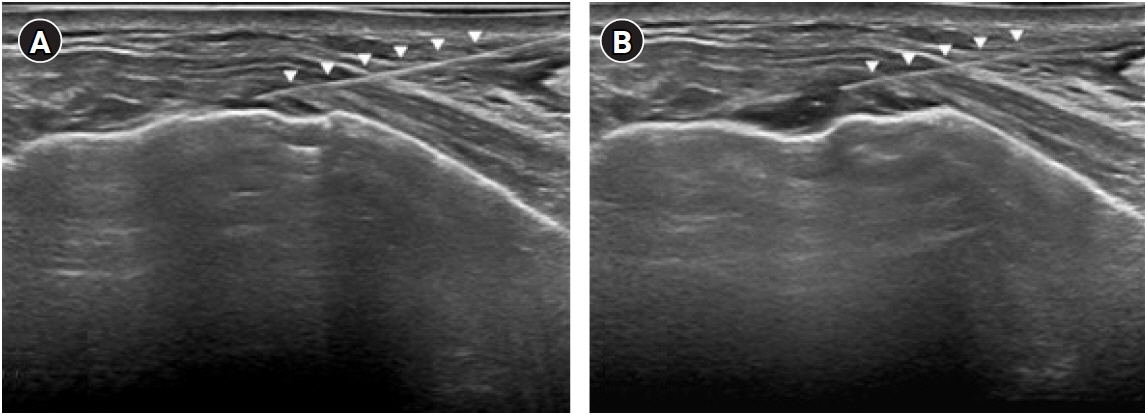

Pleurisy is an inflammation of the parietal pleura and is characterized by pleuritic pain. The most common cause of pleurisy is infection; other causes include rheumatoidarthritis, malignancy, rib fractures, or trauma. Possible causes of chest pain associated withgolf include costochondritis, stress fractures of the ribs, intercostal muscle strain, or, rarely,Tietze’s syndrome and slipping rib syndrome.Case: A 64-year-old female presented with intractable chest pain that began 4 months priorwhile playing golf. No specific cause was found after various examinations. There was persistent pain despite medical treatment. Ultrasonography (US) was performed over the painful areas, which revealed focal pleural effusions. A mixture of ropivacaine and triamcinolonewas injected into the focal pleural effusions using US guidance, which dramatically relievedher pain.Conclusions: This case demonstrates that US can be used as a diagnostic and therapeuticmodality for intractable chest pain with an undetected pathology.